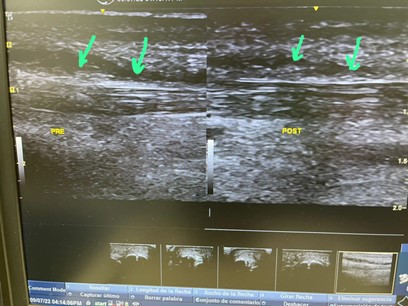

Usuwanie rozlewów Morel Lavallee za pomocą pompy diamagnetycznej

Opis Patologii:  leczenie wycieku Morela Lavallé

Podsumowanie: Leczenie Pompą Diamagnetyczną CTU MEGA 20. Pierwsza część zdjęcia jest wykonywana tuż po pojawieniu się urazu. Druga część obrazu przedstawia ewolucję wycieku po 30 minutach stosowania pompy. Dlatego różnica pomiędzy pierwszą częścią obrazu USG a drugą wynosi zaledwie 40 minut